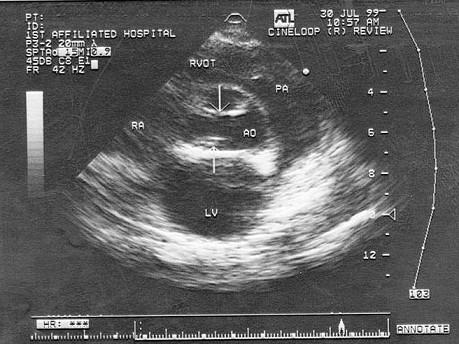

该病例最可能诊断?(?)A.主动脉瓣钙化B.先天性主动脉瓣畸形(二叶式)C.风湿性瓣膜病D.主动脉瓣脱垂E.主动脉窦瘤

问题 该病例最可能诊断?(?)

选项 A.主动脉瓣钙化 B.先天性主动脉瓣畸形(二叶式) C.风湿性瓣膜病 D.主动脉瓣脱垂 E.主动脉窦瘤

答案 B